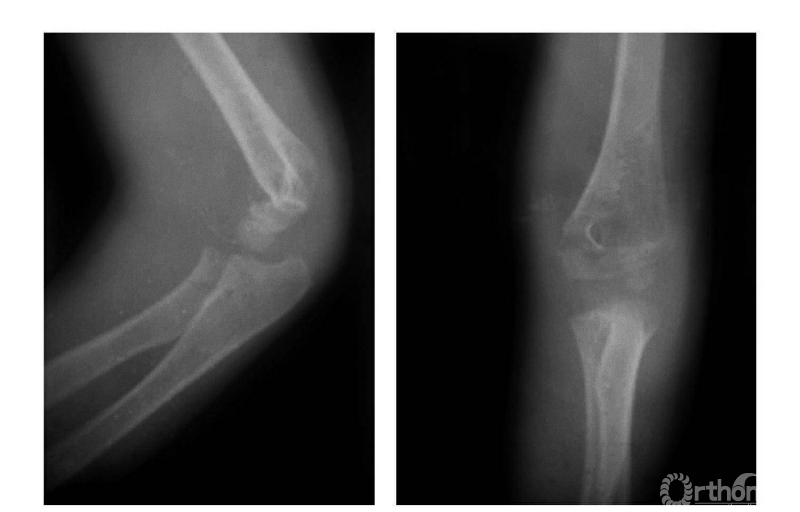

四、屈曲型

例:肱骨下端骨骺分离伴前臂向前移位(图4)。

图4